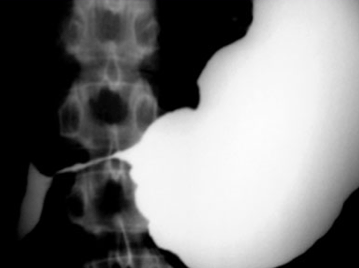

What does this image show you?

What is the difference between these two images? Why is this important?